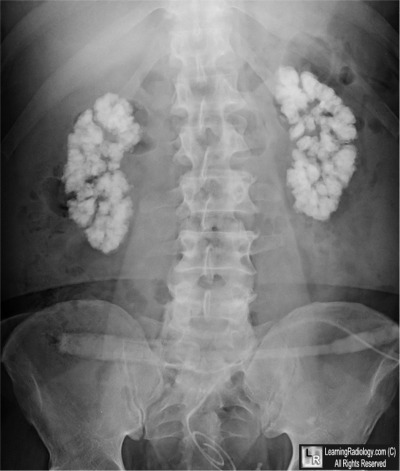

Frontal view of abdomen

5. Medullary Nephrocalcinosis

Medullary Nephrocalcinosis

- Increased calcium content of kidneys

- Usually applies to a generalized, rather than localized, increase in renal calcium content

- Macroscopic nephrocalcinosis is nephrocalcinosis visible without magnification discovered by radiography, ultrasonography, or at autopsy

- Macroscopic nephrocalcinosis can affect either cortex or medulla

- Medulla more common